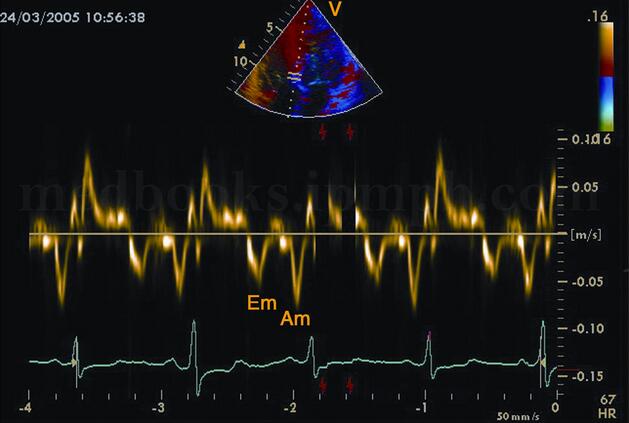

5﹒组织速度成像(TVI)正常人二尖瓣环组织多普勒Em峰>Am峰(图2‐1‐194)。扩张型心肌病室间隔二尖瓣环水平组织多普勒Em峰<Am峰(图2‐1‐195),等容舒张期延长。

图2‐1‐194 组织多普勒成像正常人二尖瓣环水平组织频谱多普勒,Em>Am

图2‐1‐195 组织多普勒成像扩张型心肌病患者二尖瓣环水平组织多普勒,Am>Em